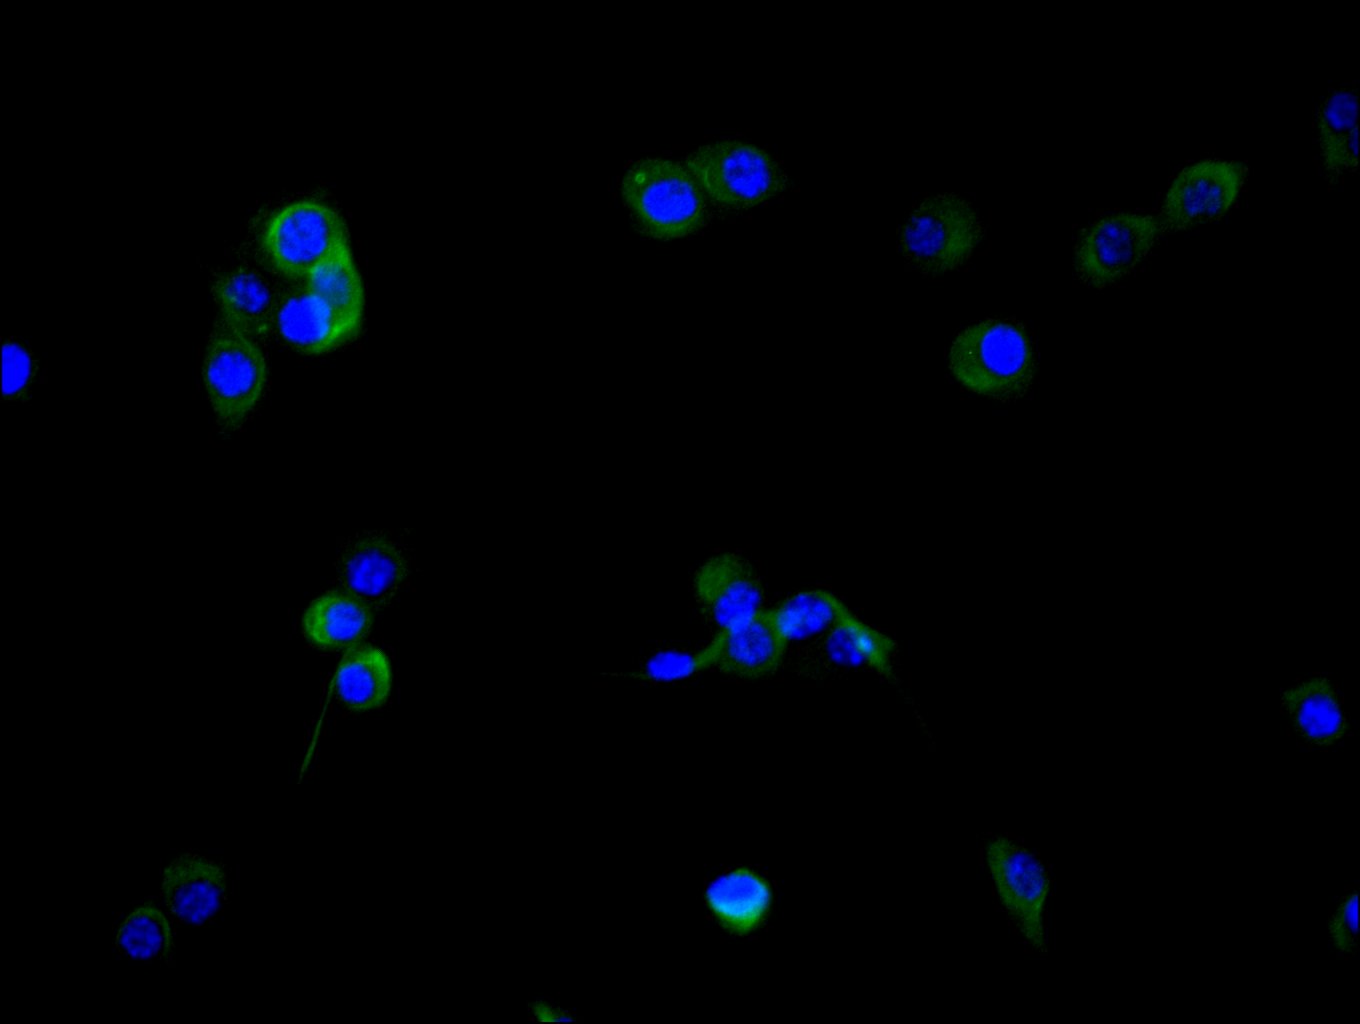

Immunofluorescence staining of NIH/3T3 cell with CSB-RA008424MA2HU at 1:30 ,counter-stained with DAPI. The cells were fixed in 4% formaldehyde, permeabilized using 0.2% Triton X-100 and blocked in 10% normal Goat Serum. The cells were then incubated with the antibody overnight at 4°C. The secondary antibody was Fluorescein (FITC) AffiniPure Goat Anti-Human IgG, Fcγ fragment specific.